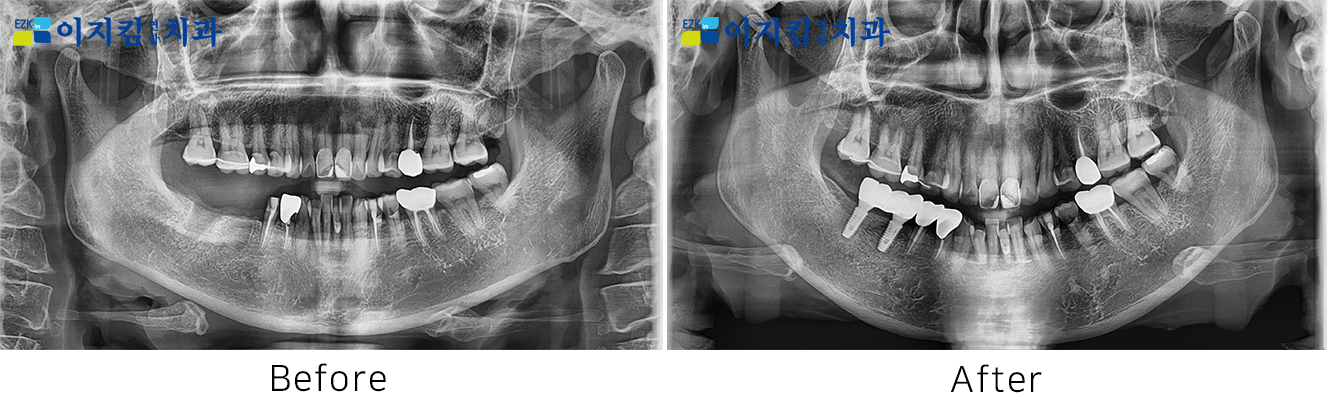

ÀÓÇöõÆ® Àü ¡¤ ÈÄ »çÁø

[

Á¶È¸¼ö : 3310

]